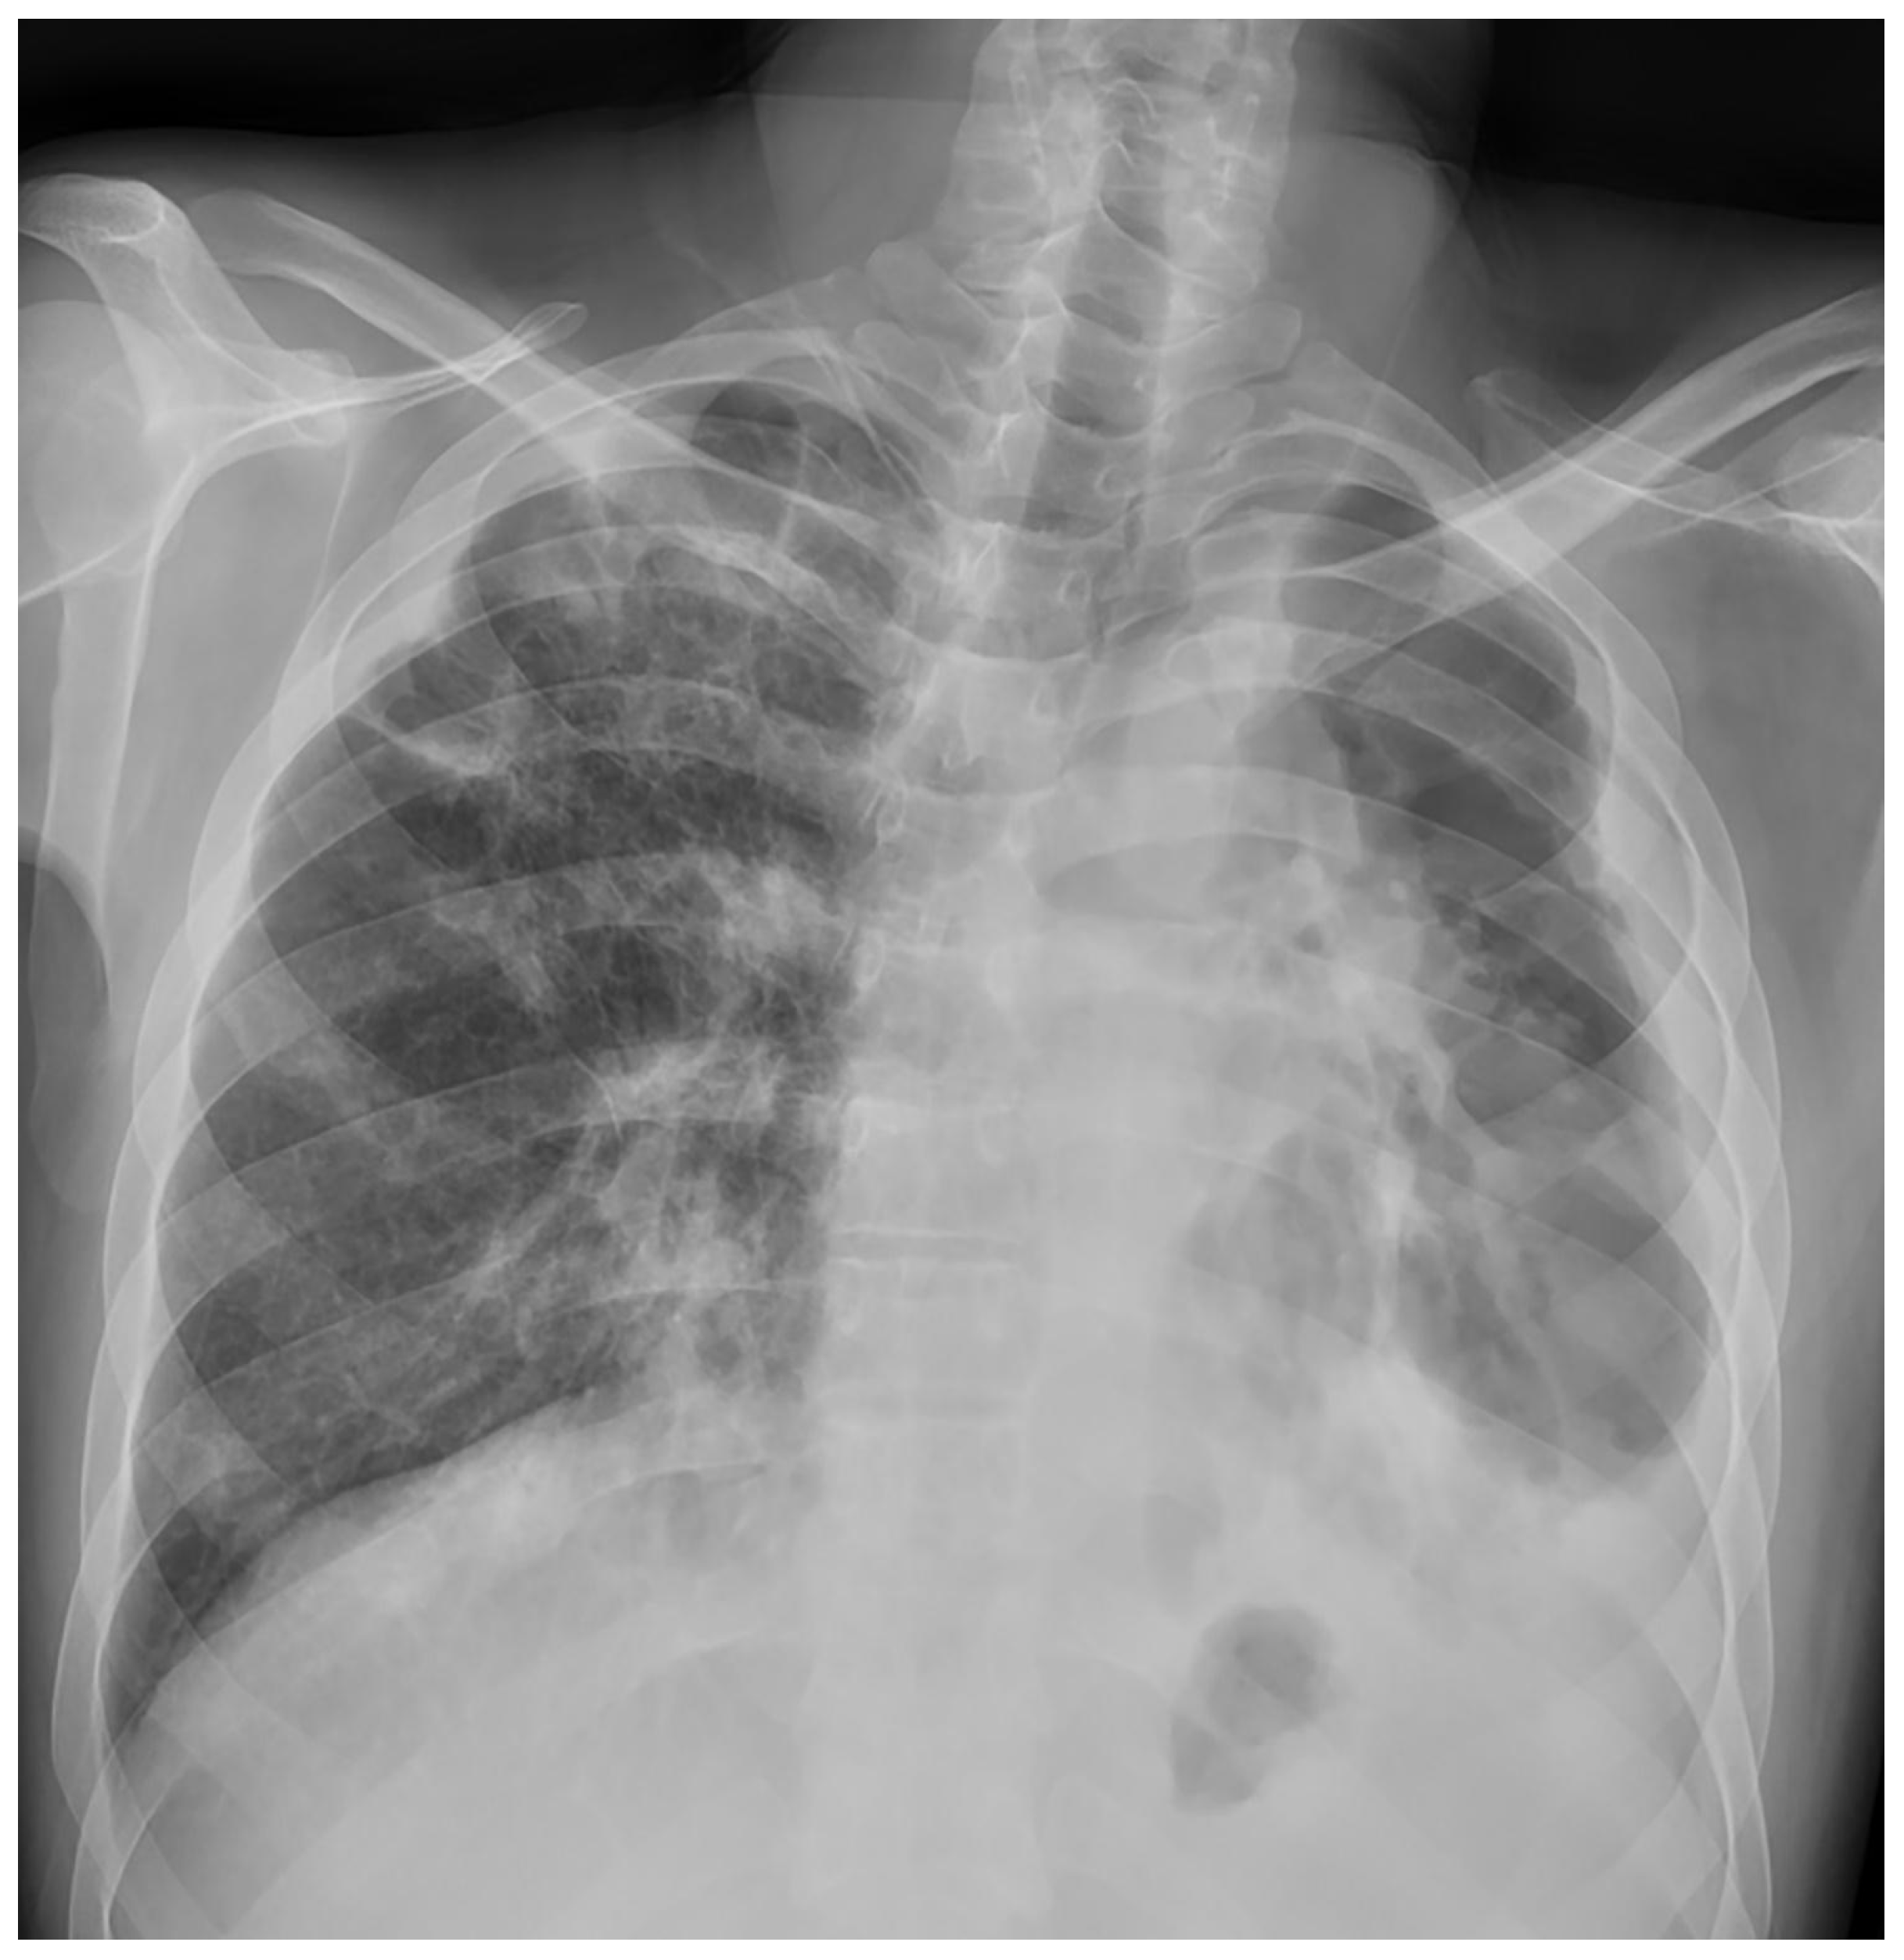

Treatment results of seven patients were reported as follows; two patients as not evaluated (returned to their home country), two patients as completion of treatment, and three patients as cured. The duration of treatments was planned as nine months, and the treatment of the patient with FQ and Z resistance (case 7) continued for 12 months. No recurrence was detected in the first-year follow-up of the five patients who could be followed. Regarding Case 4’s chest X-ray images at the beginning and the 59th day of the treatment (Figure 1 and Figure 2) and Case 7’s chest X-ray images at the beginning and the 12th month of the treatment (Figure 3 and Figure 4) a significant radiological improvement was observed.

Figure 2. Case 4, 59th day of the treatment.